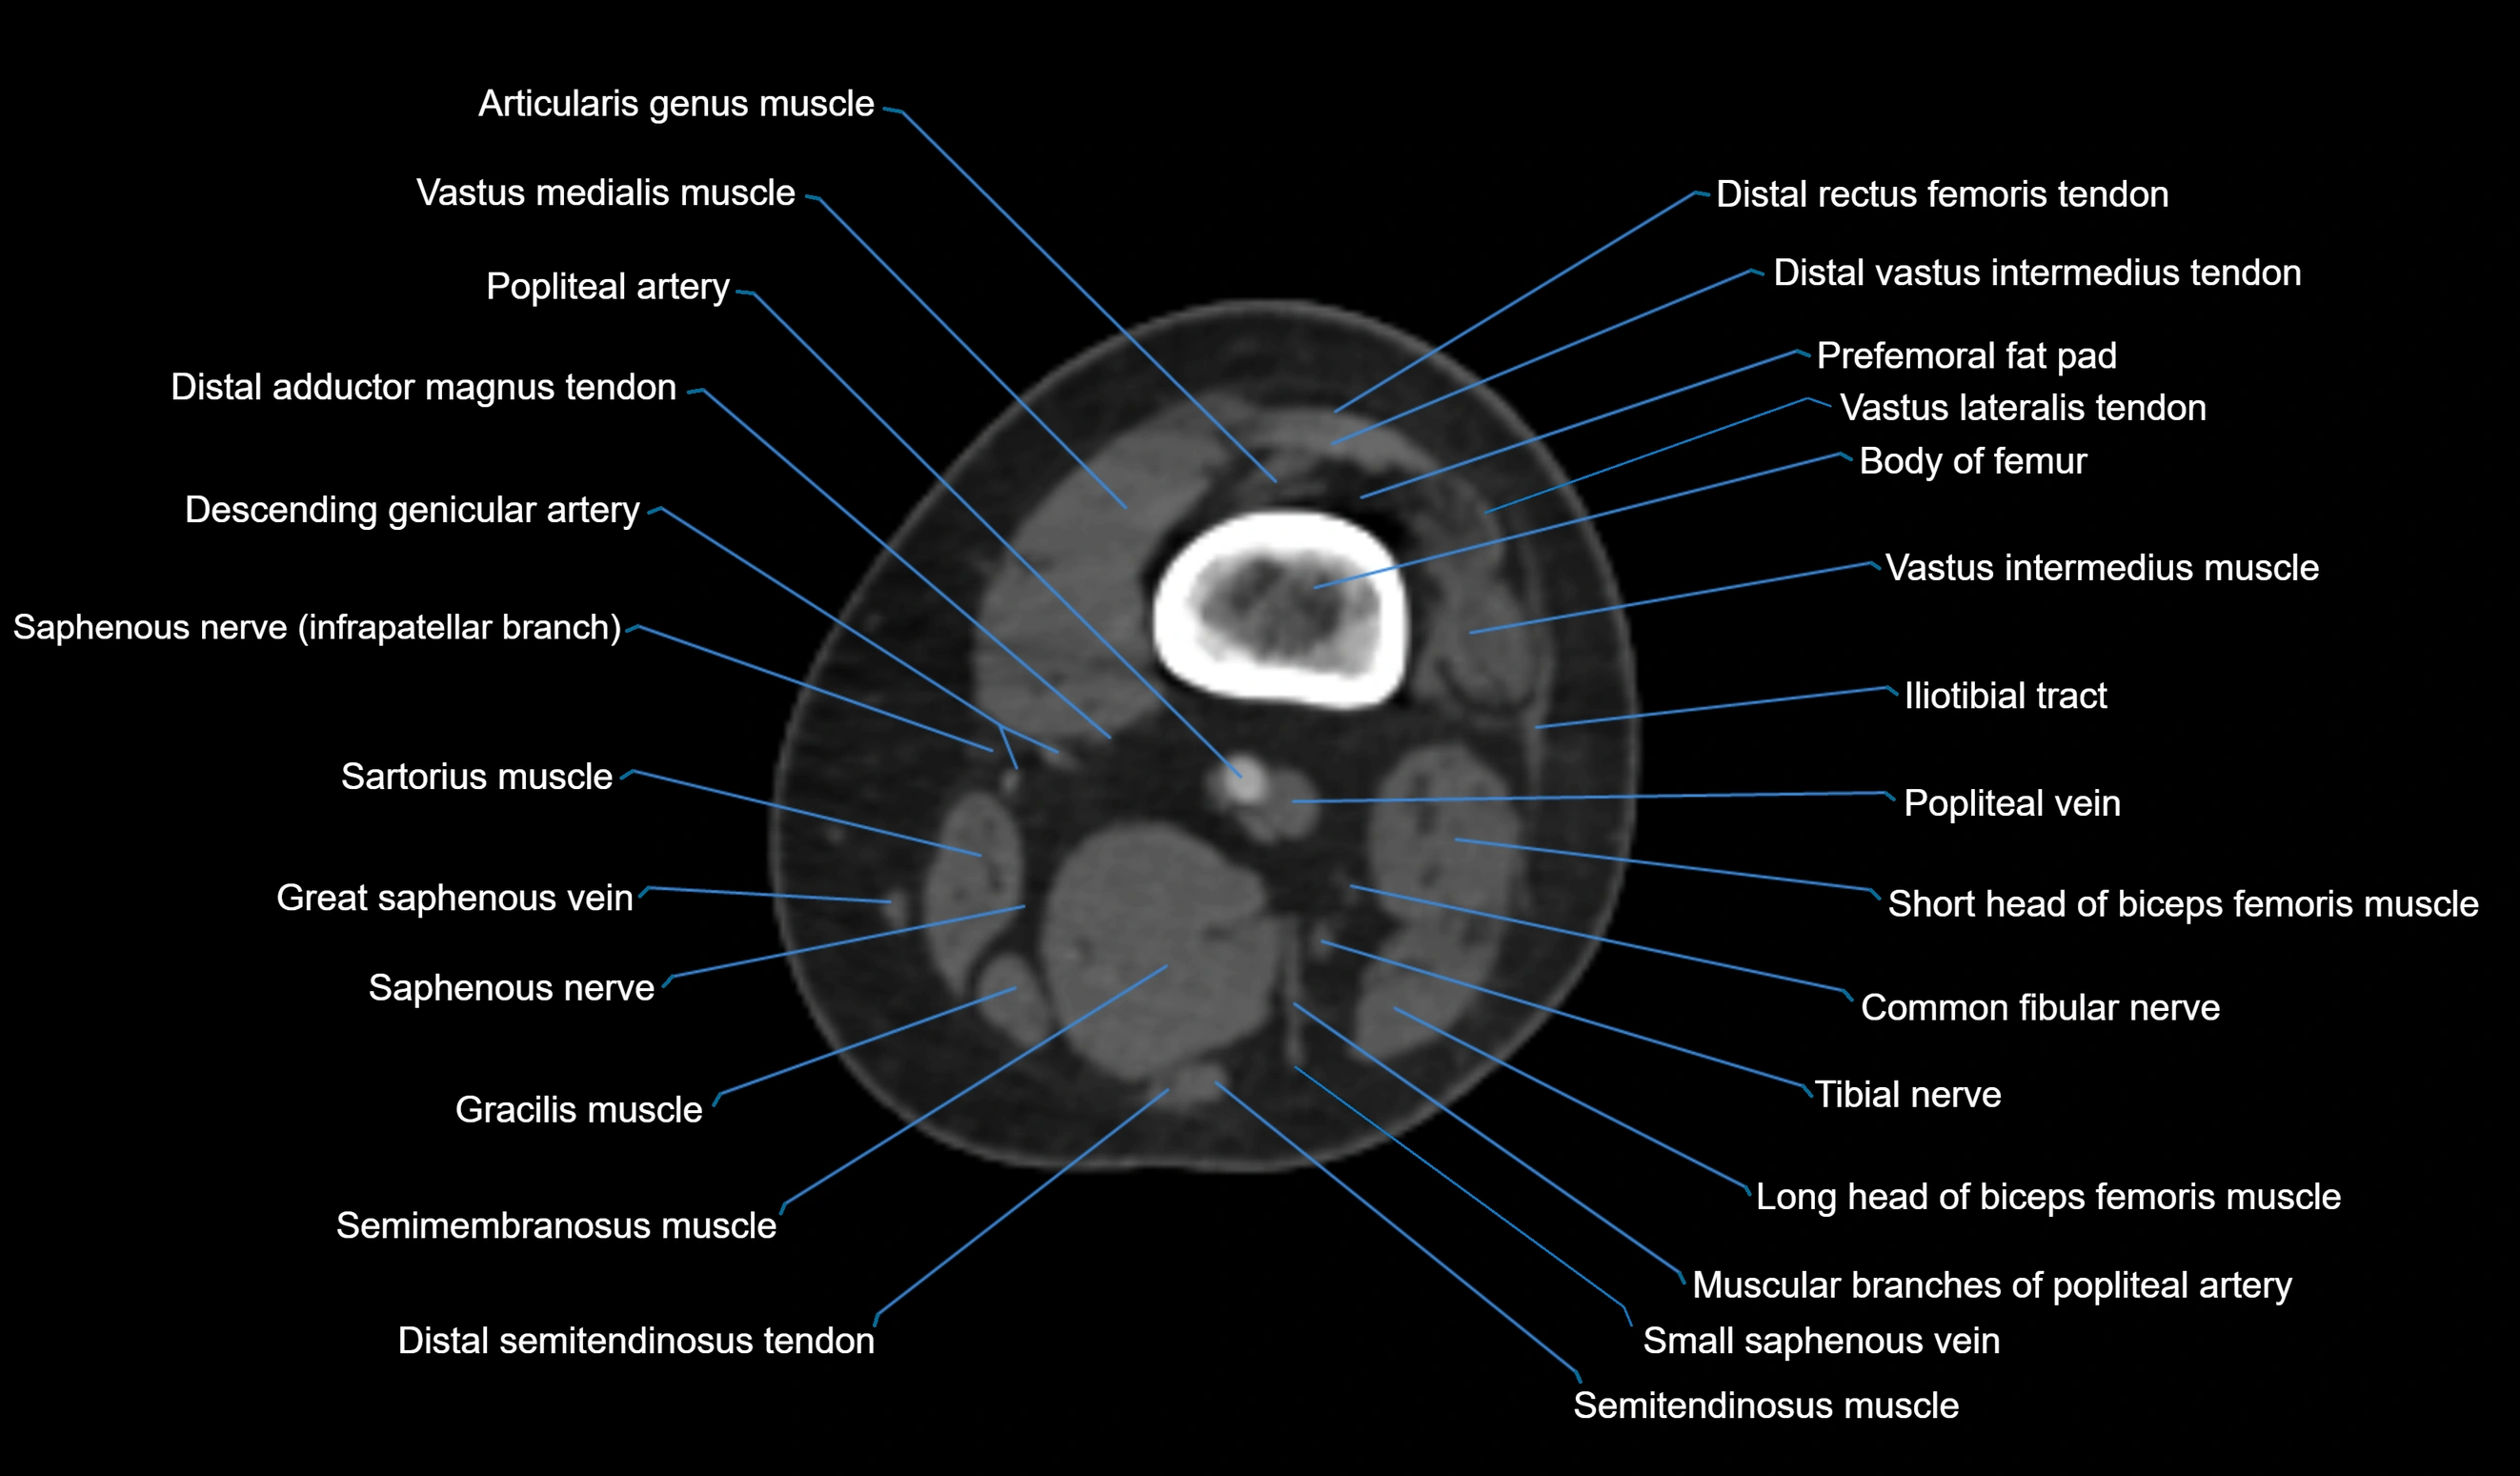

CT VRT 3D image

CT image